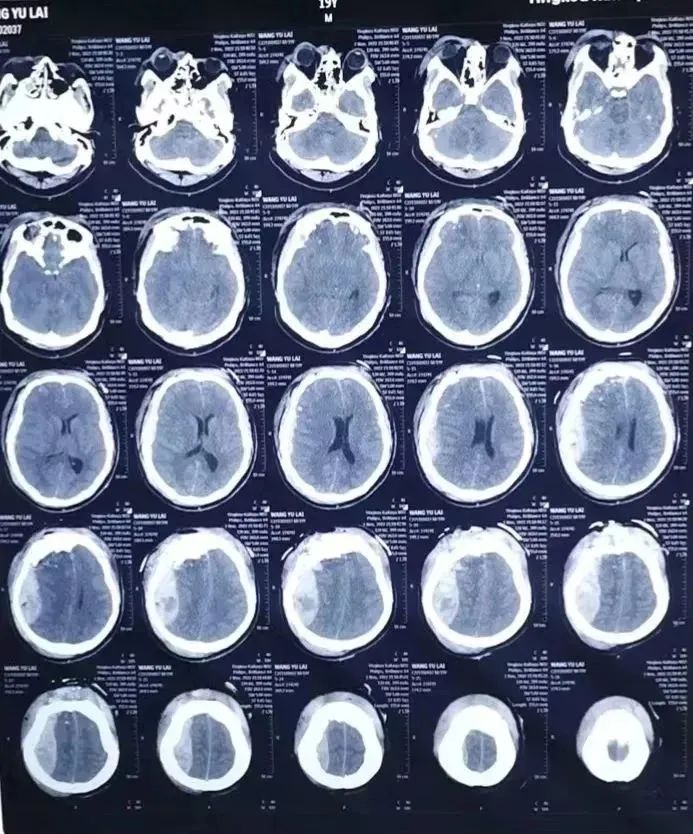

病例二

19岁男孩遭遇车祸,开放性重度颅脑损伤,开颅手术顺利清除血肿。

开放性重度颅脑损伤、颅骨开放粉碎凹陷性骨折、右额叶多发脑挫裂伤、右额顶部急性硬膜下血肿......

今年19岁的小王骑电动车时不慎与汽车相撞,头部流血不止,120接来我院,入院时已经陷入昏迷,前额部有一15cm长裂口,颅骨粉碎,且有部分脑组织流出,病情危重,随时有生命危险,病情十分危重,需立即行手术治疗。

(术前影像报告)